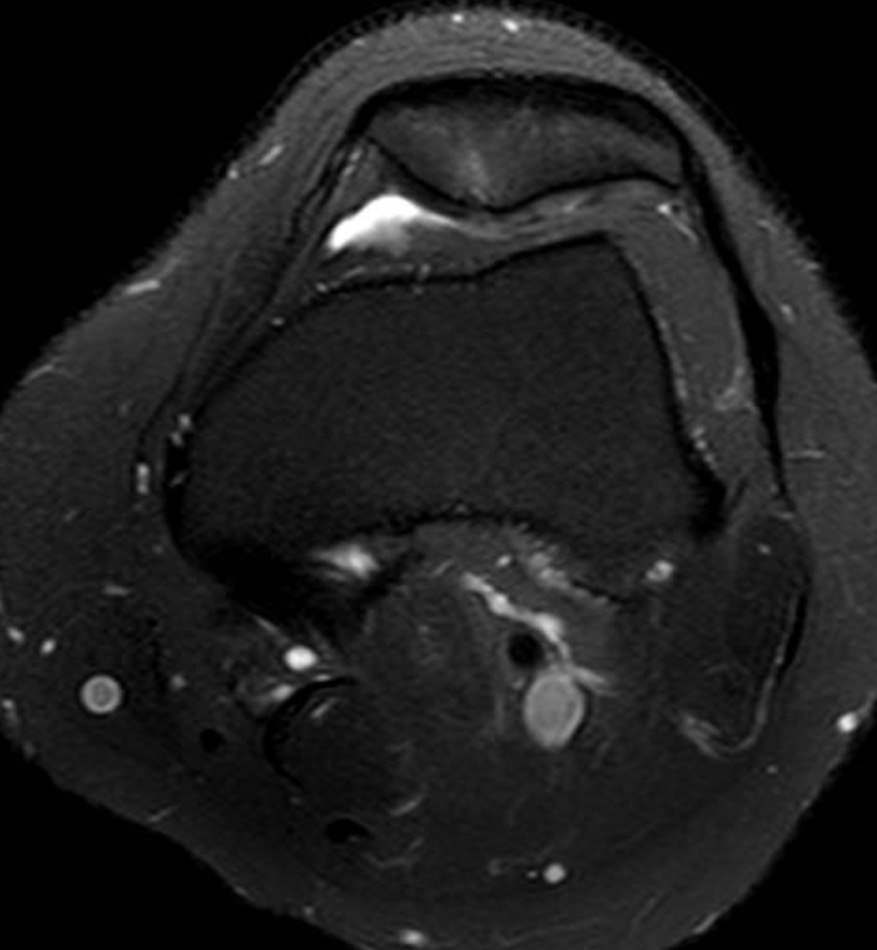

Condromalacia patelar

Também chamada de condropatia patelar. Ocorre quando a cartilagem que reveste a patela começa a sofrer desgaste.

Porém, para saber adequadamente o grau da lesão (que pode ser de 1 a 4 conforme a gravidade) e o motivo pelo qual está se desenvolvendo, exames de imagens são necessários.